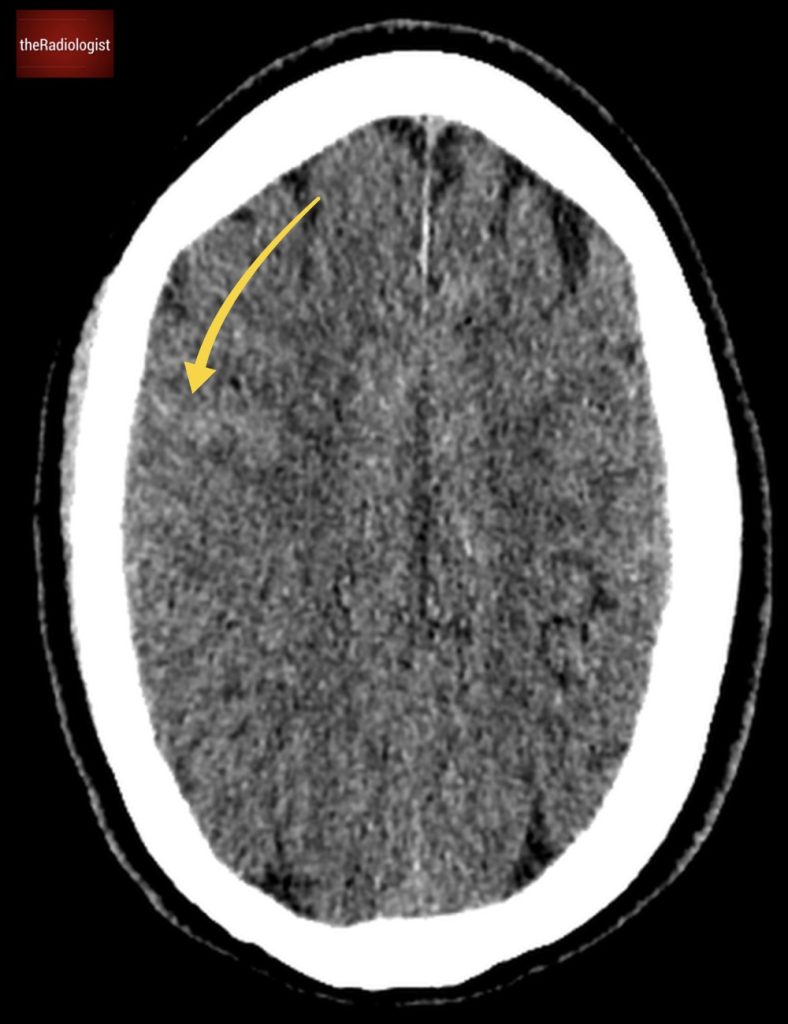

Due to pain the patient could only tolerate a few STIR sequences so we don’t have a complete scan but have a look at this axial STIR sequence below. We have high STIR signal within the right psoas with locules suggesting abscess formation.

Have a look at this axial STIR image from the MRI scan. Here we have high SITR signal within the right psoas with locules suggesting abscess formation.

If we look at a lateral STIR sequence of the lumbar spine, we can see high signal in the lateral aspect of the L3-4 disc which is continuous with the abscess formation within the right psoas. This highly suggests a spondylodiscitis as the primary pathology leading to secondary psoas abscess.

When we scroll through this sagittal STIR sequence of the lumbar spine we will see high signal within the L3-4 disc adjacent to the right psoas abnormality.